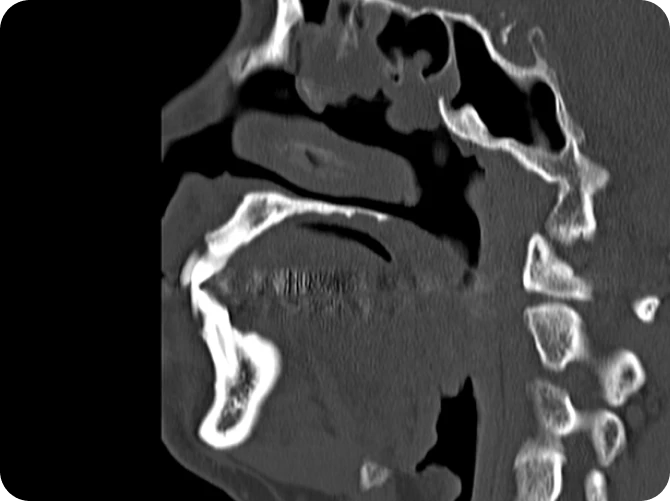

CT

코와 부비동의 농과 물혹 확인 및 축농증 감별 진단